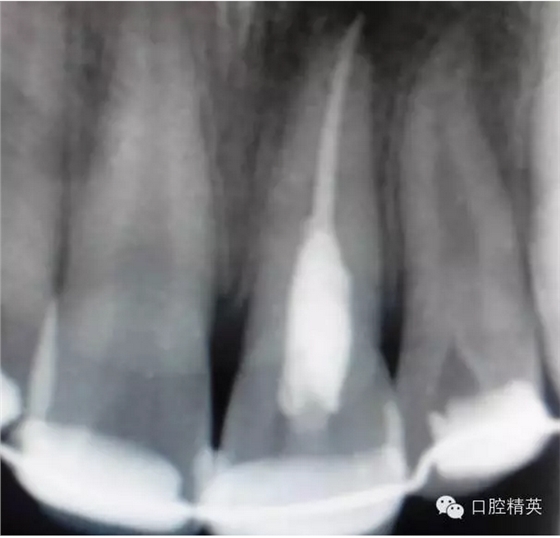

x線檢查:21牙槽窩空虛,窩內(nèi)未見其他遺留物。

圖3.患者21根尖片,牙槽窩空虛,無變形。

圖18.復(fù)位臨時固定后的x線根尖片?;颊哐栏c牙槽窩吻合。

圖23.樹脂+牙弓夾板固定完成后的x線片影像

圖5.拆除樹脂夾板前的x線根尖片影像,21根尖出現(xiàn)少許吸收。大家擔(dān)心的情況出現(xiàn)了。